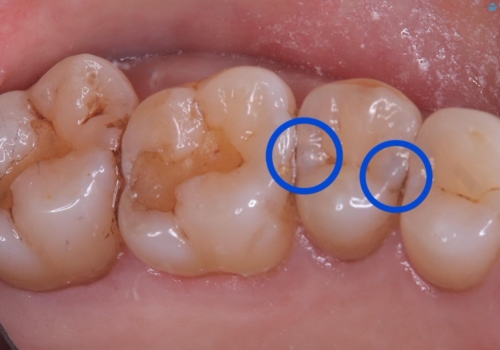

- 主訴:海外に行く前に虫歯があるなら全部しっかり治したい。

右上5番にう蝕があり、審美性・適合性・材料安定性の高いセラミックインレーでのやり替えとなりました。

右上5番の近遠心にう蝕が認められたため、CR裏層の後MOD窩洞のセラミックインレーとしました。